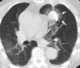

Metastasis to heart

Lung cancer, also known as lung carcinoma, is a malignant lung tumor characterized by uncontrolled cell growth in tissues of the lung. This growth can spread beyond the lung by the process of metastasis into nearby tissue or other parts of the body. [Source: Wikipedia ]